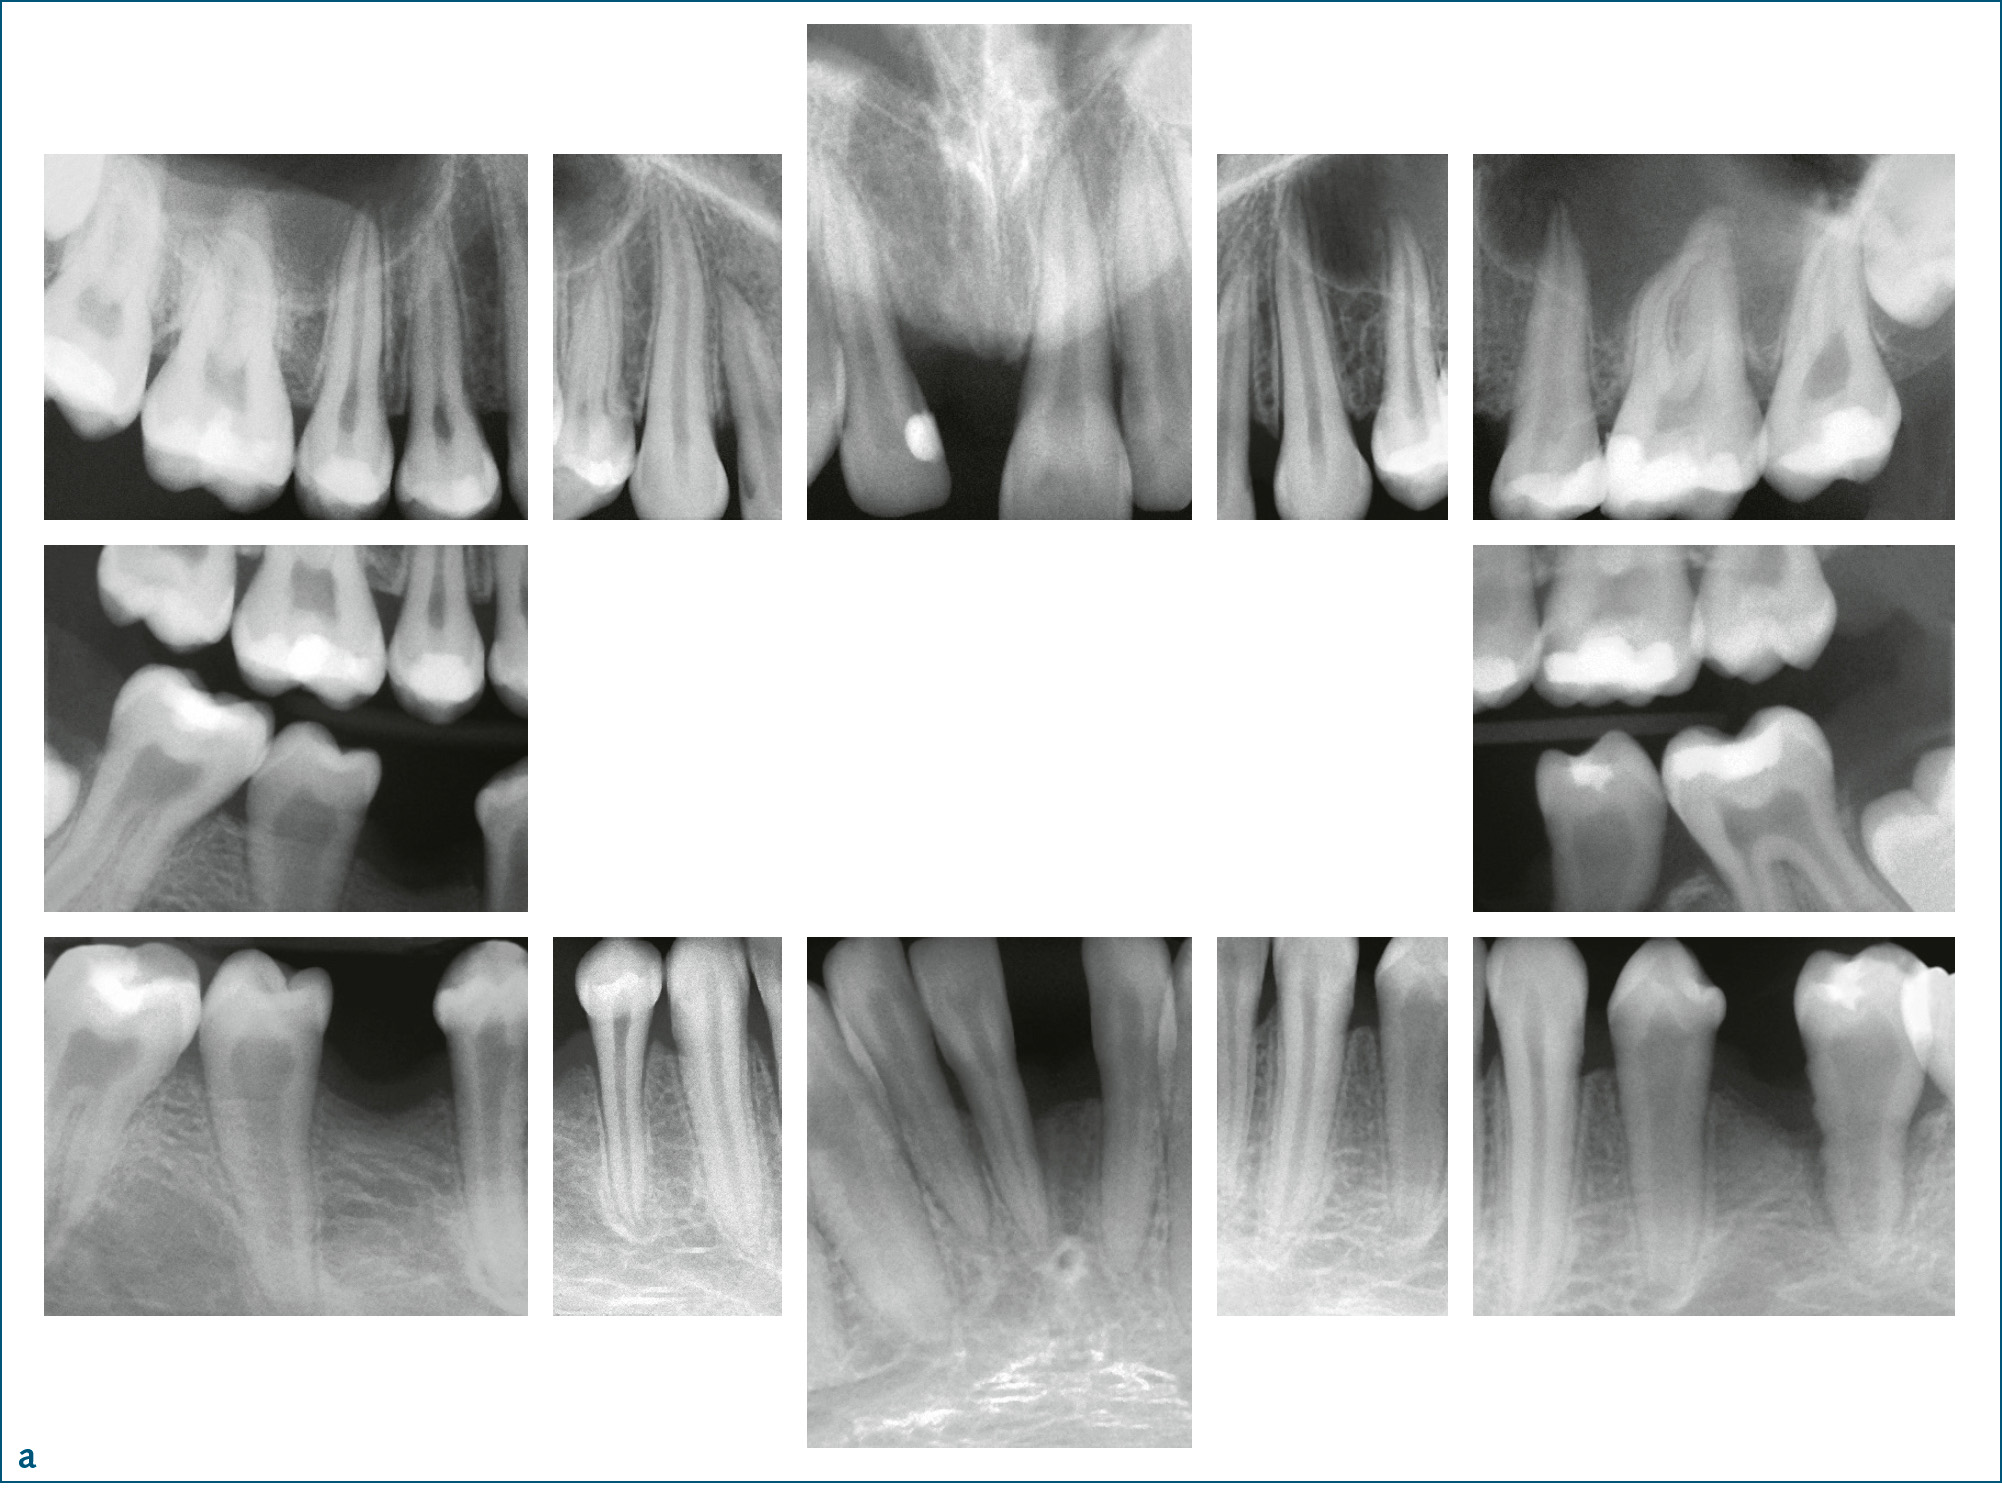

Symptomatik: Aktuell werden 6 verschiedene Formen unterschieden (Tab. 1). Die klinischen Ausprägungen reichen von der Todgeburt ohne Mineralisation der Knochen bis zu spät im Erwachsenenalter auftretenden Symptomen. Je ausgeprägter die Funktionsstörung der AP, desto schwerer verläuft die Hypophosphatasie. Während es bei der letalen perinatalen HPP zum Tod in utero oder nach wenigen Tagen zum Tod durch respiratorische Komplikationen kommt, tritt bei der benignen pränatalen HPP eine spontane Verbesserung der skelettalen Symptome ein. Patienten mit infantiler HPP erscheinen bei Geburt normal, entwickeln aber während der ersten 6 Lebensmonate die Symptome der HPP. Kleine Statur und vorzeitiger Milchzahnverlust sind häufig. Die KindheitsHPP ist durch eine lange Schädelform (Dolichocephalie) bedingt durch vorzeitige Mineralisation der Sagittalnaht, vergrößerte Gelenke, verspätetes Laufenlernen, kleine Statur und Watschelgang gekennzeichnet. Häufig treten Frakturen und Knochenschmerzen auf. Auch hier sind kleine Statur und vorzeitiger Milchzahnverlust, der zumeist bei den Schneidezähnen anfängt, häufig (Abb. 2). Sekundäre metabolische Entzündung in den Knochen und Hyperprostaglandinismus sind verbreitet. Die Erwachsenenform der HPP wird erst im mittleren Lebensalter symptomatisch. Häufig sind Fußschmerzen durch Ermüdungsbrüche des Metatarsus (Mittelfuß) oder Oberschenkelschmerzen durch Pseudofrakturen des Femur die ersten Beschwerden. Bei genauer Erhebung der zahnärztlichen Anamnese stößt man häufig auf vorzeitigen Verlust der Milchzähne. Die Odontohypophosphatasie ist durch vorzeitigen Verlust der Milchzähne bei komplettem Erhalt der Wurzel, großen Pulpakammern und starker Karies gekennzeichnet (Tab. 1). Die biochemischen Marker dieser Patienten unterscheiden sich nicht von denen der Kindheits- bzw. Erwachsenenform.

Abb. 2a bis c 14-jähriger männlicher Patient mit Kindheits-Hypophosphatasie. Die Beweglichkeit der Schultergelenke ist eingeschränkt und der Patient ist von kleiner Statur. Anamnestisch ergibt sich ein vorzeitiger Verlust der Milchzähne: a) Röntgenstatus: Die Zähne 11, 31 und 46 fehlen, es finden sich zahlreiche Restaurationen (Kariesvorgeschichte) und große Pulpakammern. Bei den Ober- und Unterkieferschneidezähnen und bei 35 zeigt sich Knochenabbau bis ins mittlere Wurzeldrittel. Die Wurzeloberfläche von 35 erscheint unregelmäßig; b) klinische Ansicht; c) Zahn 35 nach Extraktion aufgrund eines Parodontalabszesses: unregelmäßige, atypische Wurzeloberfläche.